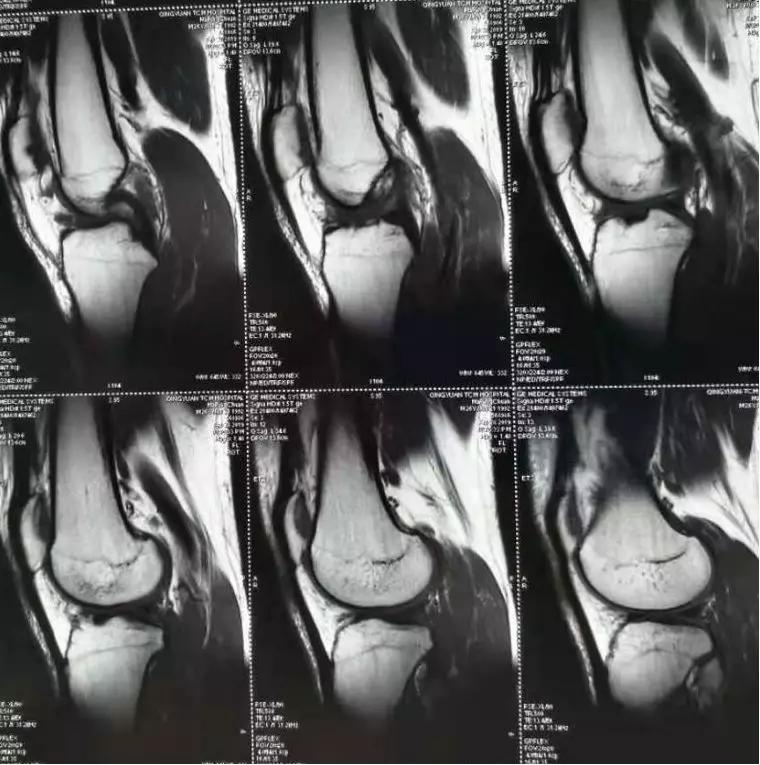

可是保守治疗一段时间后,左膝关节疼痛始终不能缓解,并伴有膝关节行走不稳感,于是马先生决定回国就医。遂至家乡当地医院就诊,完善左膝关节核磁共振(MRI)检查,但在膝关节MRI图像却发现膝前交叉韧带“不翼而飞”!

经过黄华扬教授详细的查体,结合患者的不适及影像学检查,初步考虑“左膝前交叉韧带断裂”。通过华新骨科医院关节•运动医学科专家小组谈论,建议行微创的“关节镜下左膝关节探查清理+左膝前交叉韧带重建术(取自体韧带)”。